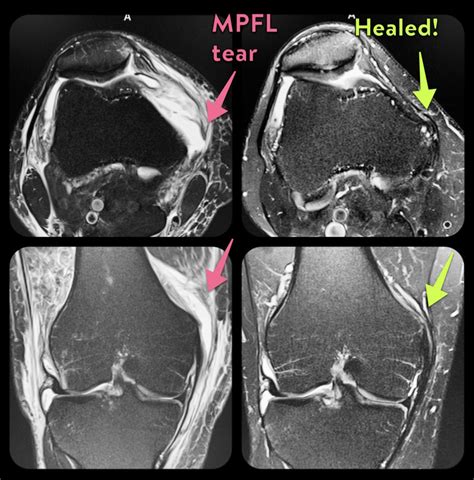

• Ligament Tears: Evaluation of the Anterior Cruciate Ligament (ACL), Posterior Cruciate Ligament (PCL), Medial Collateral Ligament (MCL), or Lateral Collateral Ligament (LCL).

• Cartilage Defects: Detecting wear and tear, or osteochondral lesions, which are often indicative of osteoarthritis.